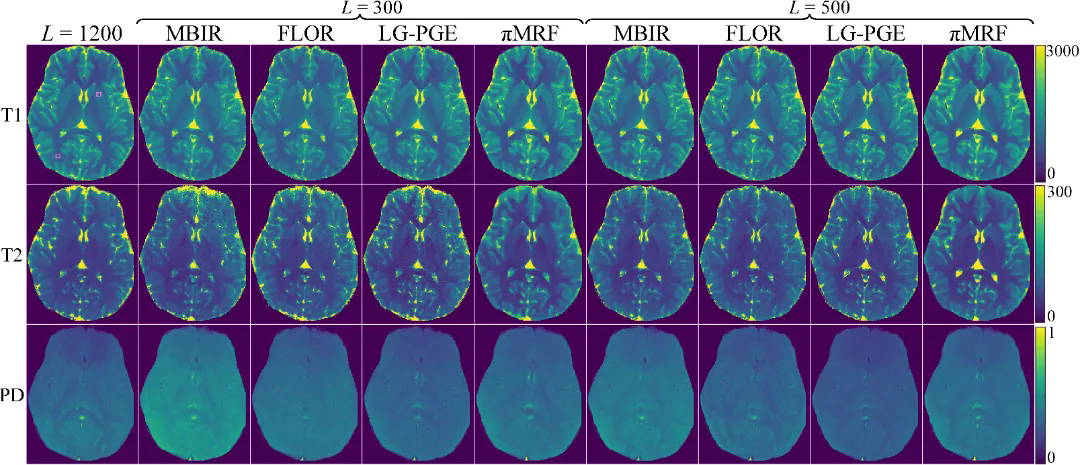

在數(shù)字仿真、水模仿體以及在體人腦實驗中,πMRF在極端欠采樣條件下均表現(xiàn)出更高的定量準確性與空間一致性,能夠穩(wěn)定恢復T1、T2和PD參數(shù)分布,并在組織邊界及病灶區(qū)域保持更可靠的細節(jié)表達,整體性能顯著優(yōu)于現(xiàn)有對比方法。上述結(jié)果表明,該研究有效緩解了 MRF 在極端欠采樣條件下面臨的不適定逆問題,展示了“物理模型與連續(xù)神經(jīng)表示深度融合”在復雜醫(yī)學成像反演任務中的應用潛力。

圖5:在體人腦實驗結(jié)果